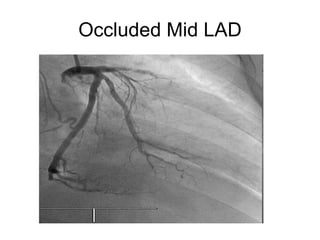

This document contains medical terms and questions related to cardiology board exams. It discusses cases involving Brugada syndrome, ventricular fibrillation treated with an implantable cardioverter-defibrillator, hyperacute anterior ST elevation myocardial infarction, pericarditis, various arrhythmias including Wolff-Parkinson-White syndrome, ectopic atrial rhythm, junctional rhythm, low voltage ECG, left bundle branch block, ventricular tachycardia, and atrial flutter.